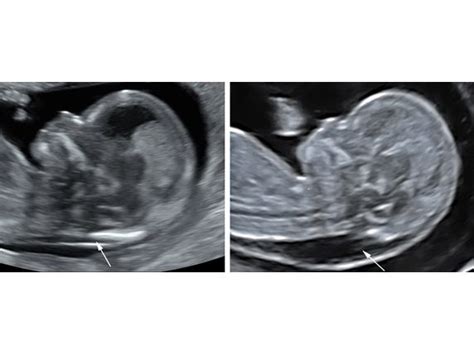

La Translucenza Nucale è un'ecografia diagnostica specializzata, eseguita tipicamente tra la 11ª e la 13ª settimana di gravidanza, più precisamente tra la 11ª settimana e 0 giorni e la 13ª settimana e 6 giorni, quando la lunghezza cranio-caudale (CRL) del feto è compresa tra 45 e 84 mm. Questo lasso di tempo non è arbitrario, ma scientificamente determinato per massimizzare l'accuratezza dell'esame. In questo periodo gestazionale, la struttura che si misura, ovvero la plica nucale, è particolarmente evidente e permette una valutazione precisa.

L'esame misura lo spessore della piega nucale nel collo del feto, un parametro importante per valutare il rischio di anomalie cromosomiche, come la sindrome di Down (Trisomia 21), ma anche la Trisomia 18 (Sindrome di Edwards) e la Trisomia 13 (Sindrome di Patau). Una translucenza nucale aumentata non è una diagnosi di per sé, ma un indicatore di un rischio potenziale più elevato, che richiede ulteriori approfondimenti. È cruciale comprendere che questo è un test di screening, il cui obiettivo è identificare le gravidanze a rischio elevato che potrebbero beneficiare di test diagnostici più invasivi e definitivi, come la villocentesi o l'amniocentesi. Non si tratta, quindi, di un test diagnostico che fornisce una risposta certa, ma piuttosto di uno strumento prezioso per stratificare il rischio.

La preparazione non è complessa: non è necessaria una preparazione specifica per la futura mamma, se non, eventualmente, arrivare con la vescica moderatamente piena per facilitare la visualizzazione dell'embrione e del suo posizionamento all'interno dell'utero. Una vescica piena può aiutare a spingere l'utero in una posizione che offre una migliore "finestra acustica" per la sonda ecografica, migliorando la qualità delle immagini ottenute. È consigliabile indossare abiti comodi che facilitino l'accesso all'addome. Durante l'esame, la mamma può sdraiarsi comodamente sul lettino, e l'ecografista mostrerà le immagini del feto su uno schermo, spiegando in tempo reale le varie strutture visualizzate e la misurazione della translucenza nucale. L'abilità e l'esperienza dell'operatore sono fattori critici per ottenere una misurazione accurata, poiché anche piccole variazioni nell'angolazione della sonda o nella selezione del piano di scansione possono influenzare il risultato. La misurazione deve essere effettuata quando il feto è in posizione neutrale, con la testa e il corpo allineati, non flesso o esteso, per evitare letture errate.